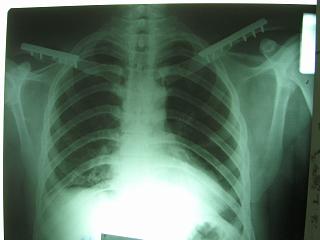

Накостный остосинтез обех ключиц в одну сессию рекон.пластиной в условиях интубационного наркоза с положительным ПДКВ (+ 5-7 мм вод. ст.) и интраоперационным контролем степени пневмоторакса. Возможно, дренирование плевральной полости слева, по результату рентгенконтроля, по Бюлау.

Справа перелом практически поперечный, можно попробовать интрамедуллярно стержнем. Личного опыта правда не имею, у нас стандартом при оперативном лечении переломов ключицы является тот же остеосинтез пластиной. Но в литературе описана методика даже закрытого остеосинтеза - так, в порядке обсуждения.

Мы очень часто сейчас оперируем ключицы . Остеосинтез реконструктивной пластиной и винтами, без иммобилизации наружной в последующем. Несращений за последние годы не наблюдали. В течение последних 2х лет прооперировали 23 перелома.

С пневмотораксом все понятно-дренировать плевральную польсть. А вот на счет ключиц действительно вопрос интересный, необходима золотая середина. Учитывая, что имеется повреждение грудной клетки, для улучшения активного дыхания необходимо будет выполнить остеосинтез обеих ключиц, накостный, реконструктивными пластинами.

Bolnogo operirovali plastinami, snimky zdes'.

CIMG1145.JPG

Похоже, все прошло по плану. Поздравляю с успешной операцией!